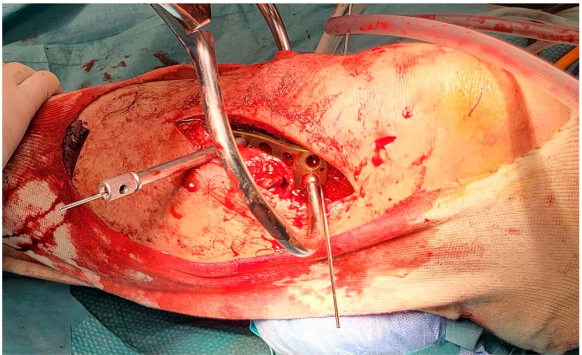

图 4一名受胫骨平台后外侧骨折影响的 42 岁男性患者的左膝,标有执行改良 Frosch 入路的解剖皮肤标志,特别是 Gerdy 结节 (GT)、股骨上髁 (FE) 和胫骨结节 (TT) 标记在左膝上 (A)。左膝前侧手术窗口(前外侧入路)的术中视图,显示在剥离 CPN 后执行胫骨前外侧钢板固定 (B)。在剥离和保护 CPN 后,通过比目鱼肌和腓肠肌外侧头之间的肌间平面进入后侧窗口的术中视图 (C)。左膝在剥离 CPN 并完成改良 Frosch 入路后外侧窗口后,胫骨平台后外侧骨折(白色箭头)的术中视图 (D)。